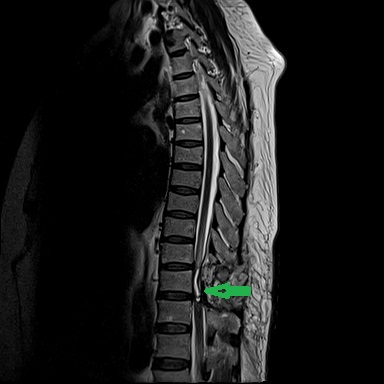

患者康婆婆(化名)今年已近70岁,因“右下肢麻木5+月加重伴疼痛3+月”前来医院治疗,行腰部核磁检查发现胸11椎体平面脊髓内囊性占位,考虑室管膜瘤的肿瘤性病变。患者下肢长期麻木伴疼痛,经神经外科医疗团队研究讨论,为患者行了微创的胸椎椎管骨质切开和脊髓内肿瘤病变的切除手术治疗,切除了患者的肿瘤后,患者下肢肌力和麻木感明显改善。

术后手术图片